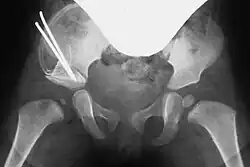

Preoperative planning involves conventional pelvic X-rays, including pelvic overview and Rippstein view images, to assess joint misalignment, severity, and surgical planning. Rippstein views provide a lateral projection of the femoral necks.[7][8]

In cases of dysplastic hip dislocation, a functional arthrography of the hip joint(s) may be performed first to assess dislocation behavior and the extent of capsular stretching or injury on X-ray. This step helps determine whether surgery is necessary and which technique to use.[7]